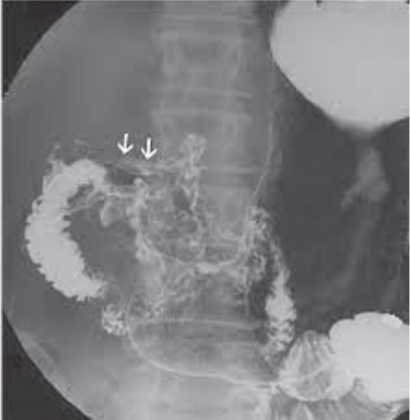

What is this

Ulcerative colitis